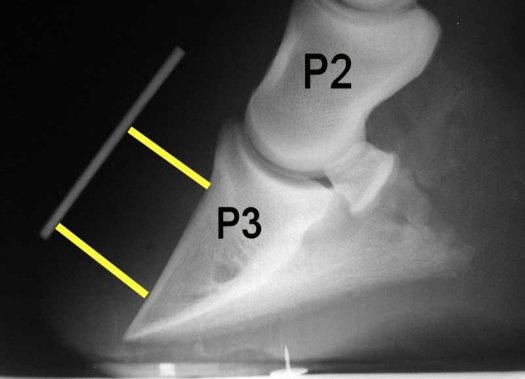

The vet will usually have placed markers on certain parts of the foot before xray to make it easier to assess the true point of frog, the angle of the outer wall and also the height of the coronary band so they can assess if the pedal bone has moved. These markers also make it easier to compare subsequent xrays at a later date.